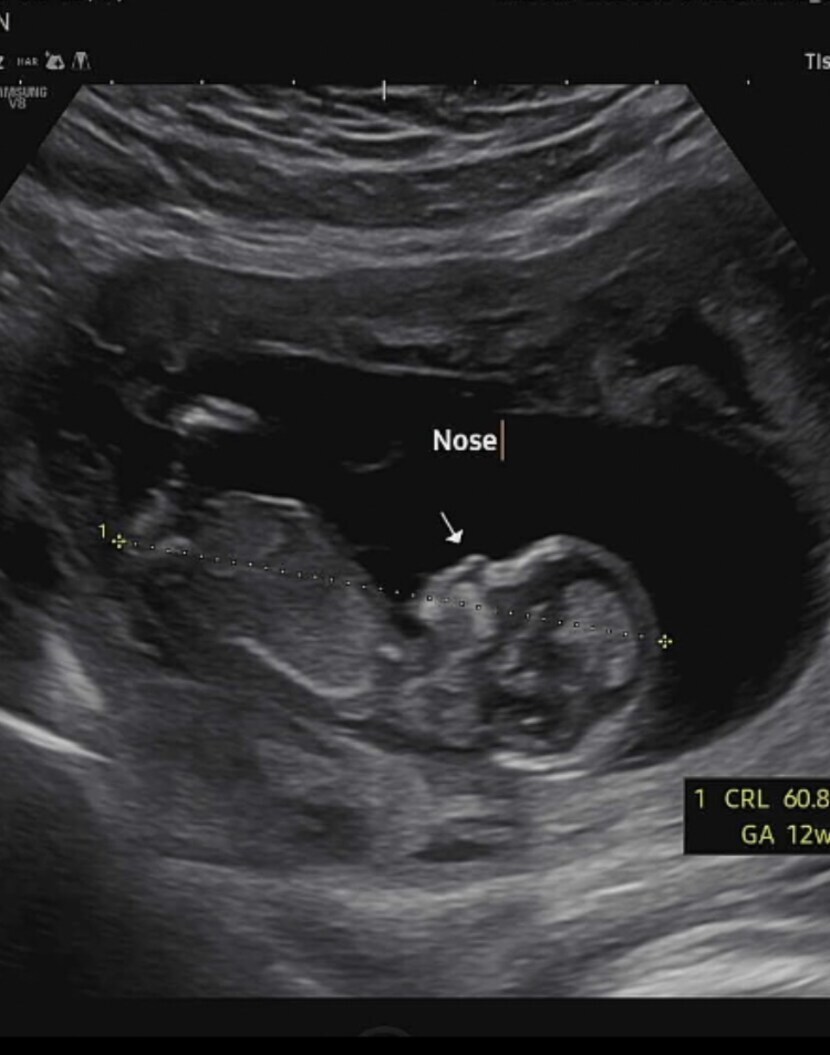

22.12.22 97 읽음 첫 입체초음파❤ 스크럼프 구독하기 0 3 콘텐츠의 수익 2 기다리고 기다리던 병원가는날!1차 기형아검사 하는날이에요 두근두근목덜미 투명대는 정상이래요코도 오똑하고 손발 모두 잘 있어요키는 6센치라네요입체초음파는 처음이라 너무 기대됐어요우리 식빵이 얼굴을 처음 보는날이에요솔직히..다른사람들 입체초음파 보면 약간...외계인같아보였는데..ㅎㅎ우리식빵이는 왜케 이쁜거죠❤??ㅋㅋㅋㅋㅋㅋ 3 0 / 300 입력